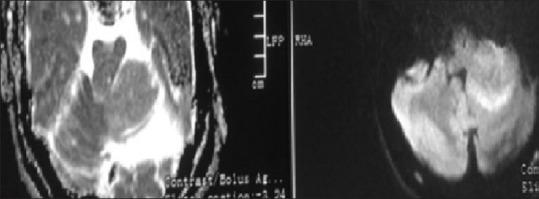

Gorlin-Goltz syndrome (GGS) is a rare autosomal dominant disorder with multisystemic involvement. It is characterized by the triad of multiple baso-cellular epitheliomas, odontogenic keratocysts (OKC) in the jaws and skeletal anomalies. Later, it was found that calcification of falx is also highly specific. We present radiological findings in case series of two cases, one with multiple OKC, calcified falx, skin lesions, and fibrous dysplasia of sphenoid and second with multiple OKC, calcified falx, vertebral anomaly and medulloblastoma.

戈林-戈尔茨综合征(GGS)是一种罕见的常染色体显性疾病,累及多系统。其特征为三联征,即多发性基底细胞上皮瘤、颌骨牙源性角化囊肿(OKC)和骨骼异常。后来发现,大脑镰钙化也具有高度特异性。我们展示了两个病例系列的影像学表现,一例有多发性OKC、大脑镰钙化、皮肤病变和蝶骨纤维发育不良,另一例有多发性OKC、大脑镰钙化、椎体异常和髓母细胞瘤。